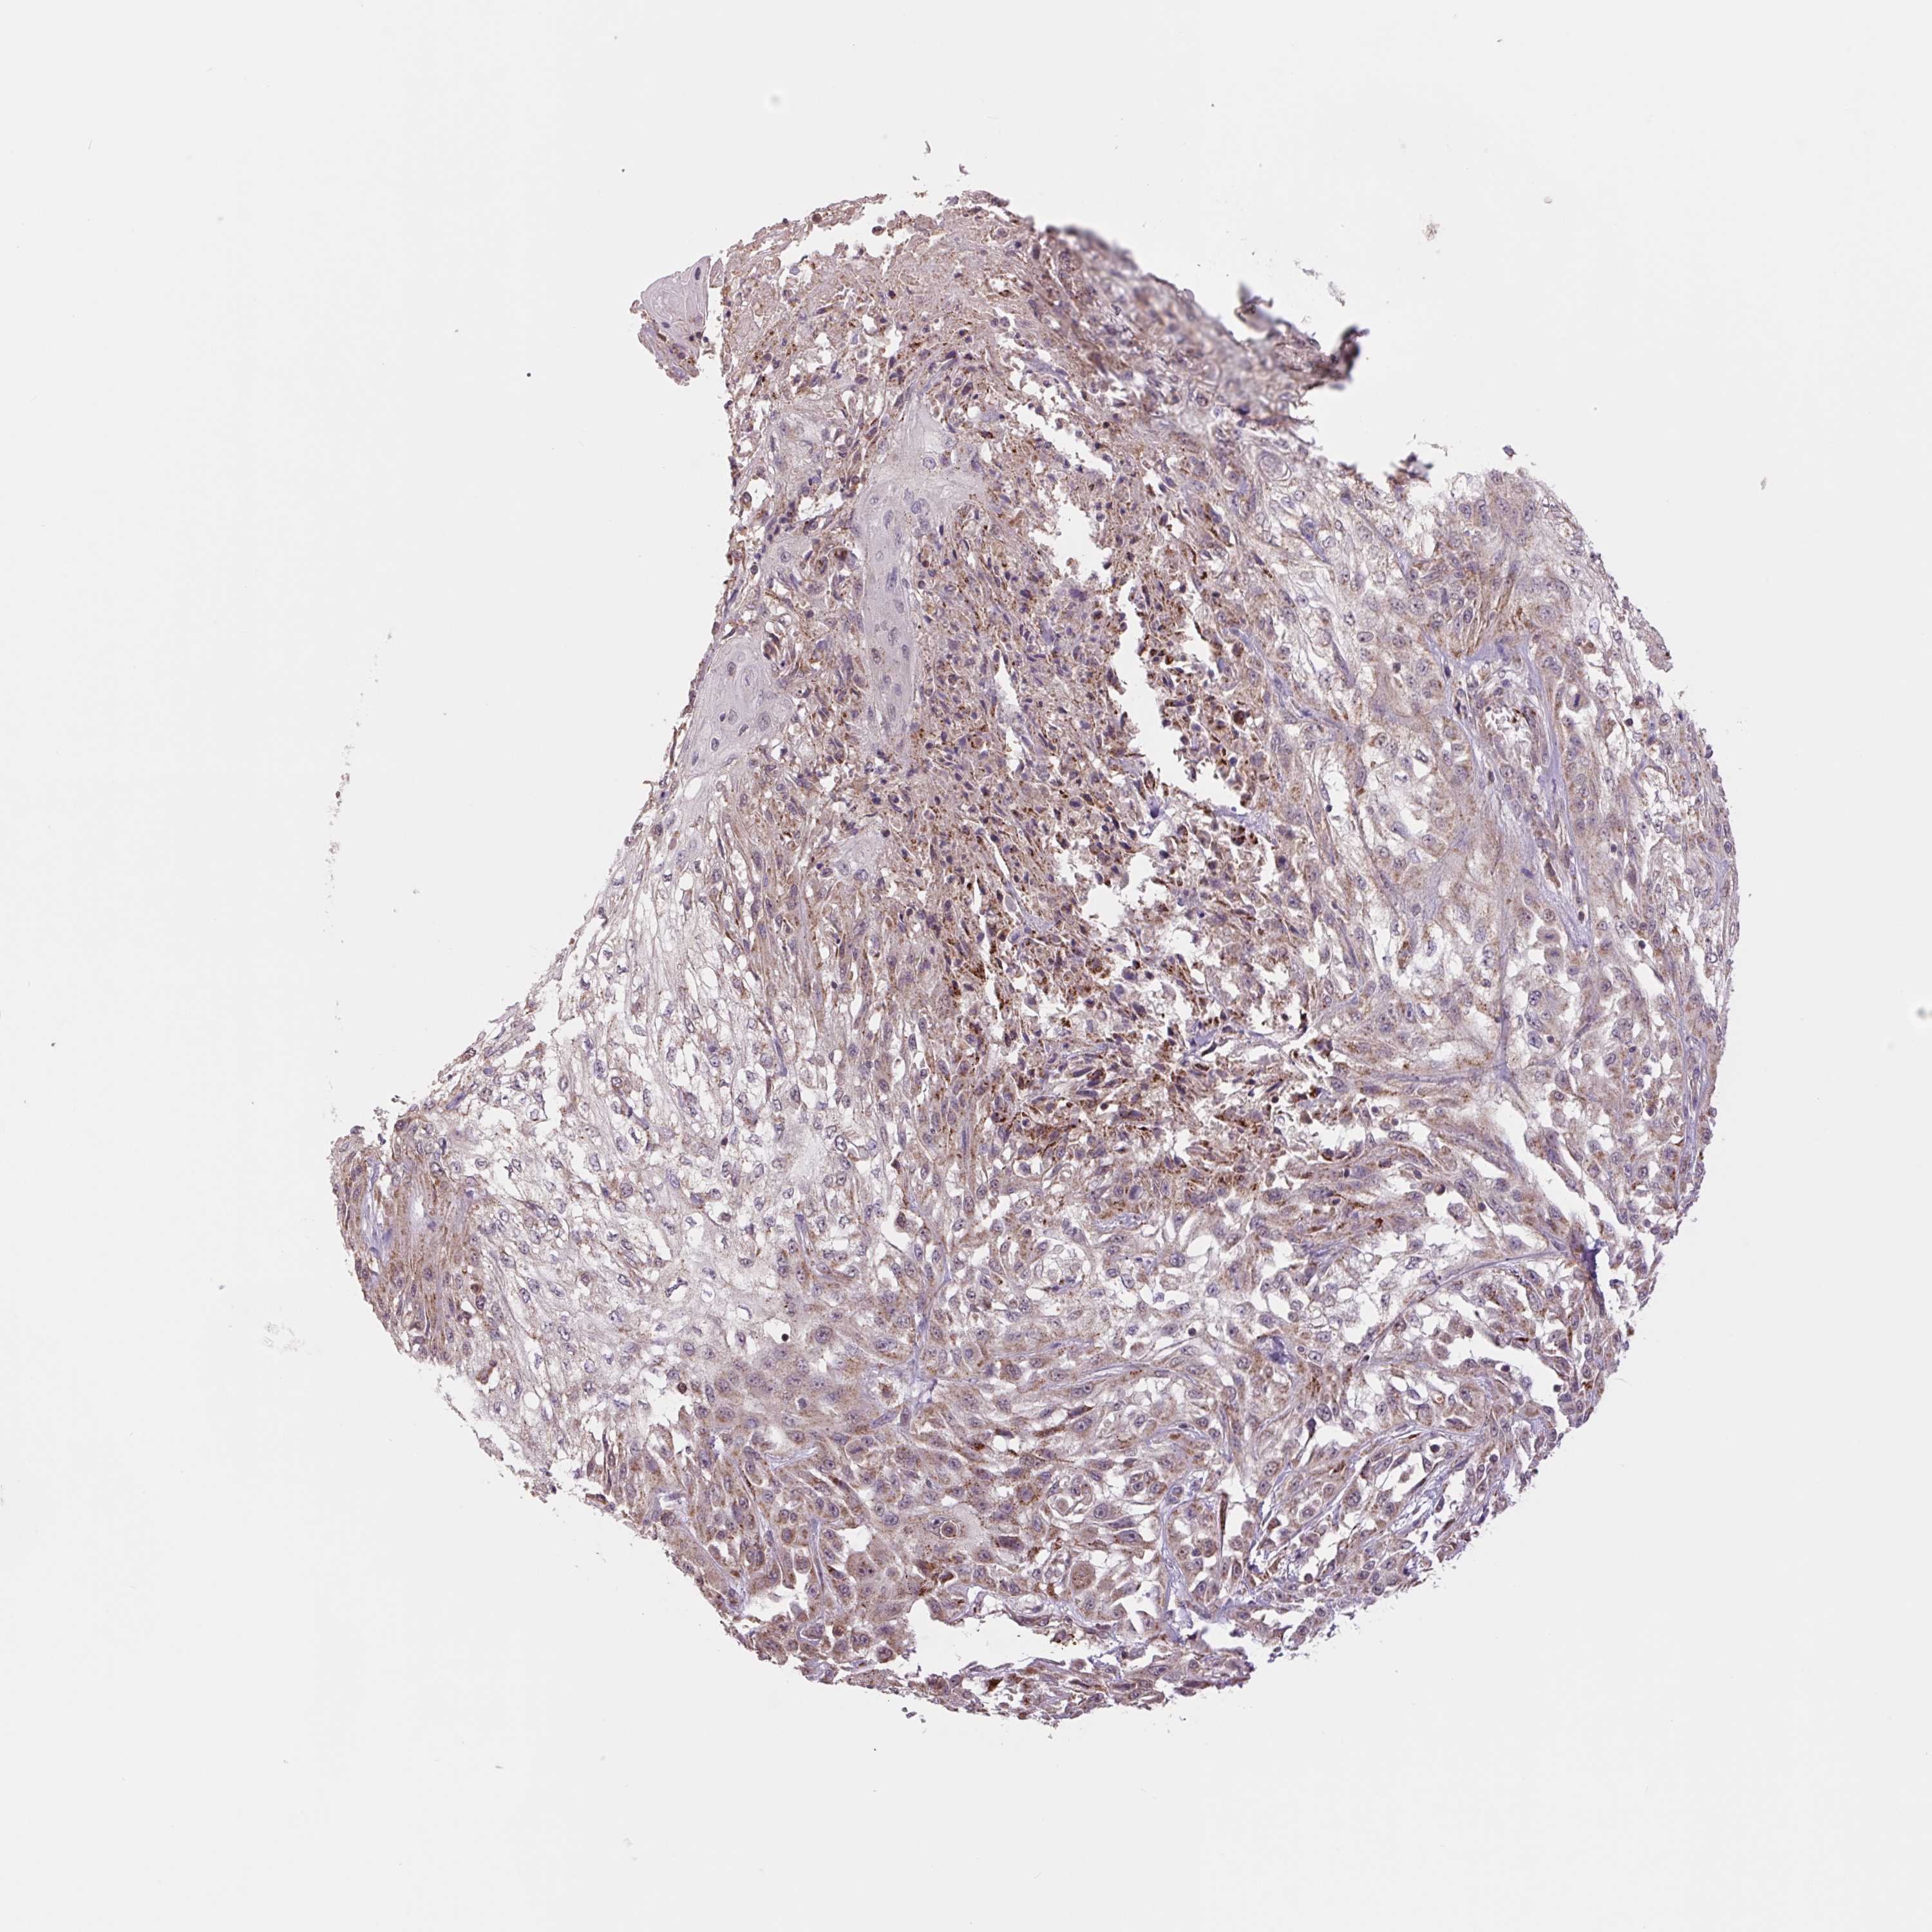

SKIN CANCER - Protein expressioni

A mouse-over function shows sample information and annotation data. Click on an image to view it in a full screen mode. Samples can be filtered based on level of antibody staining by selecting one or several of the following categories: high, medium, low and not detected. The assay and annotation is described here.

Antibody staining in the annotated cell types in the current human tissue is reported as not detected, low, medium, or high, based on conventional immunohistochemistry profiling in selected tissues. This score is based on the combination of the staining intensity and fraction of stained cells.

Each image is clickable and will lead to virtual microscopy that enables deeper exploration of all samples and also displays staining intensity scores, fraction scores and subcellular localization as well as patient and tissue information for each sample.

Antibody HPA055904

Basal cell carcinoma

Squamous cell carcinoma, NOS

Squamous cell carcinoma, metastatic, NOS

Squamous cell carcinoma in situ, NOS